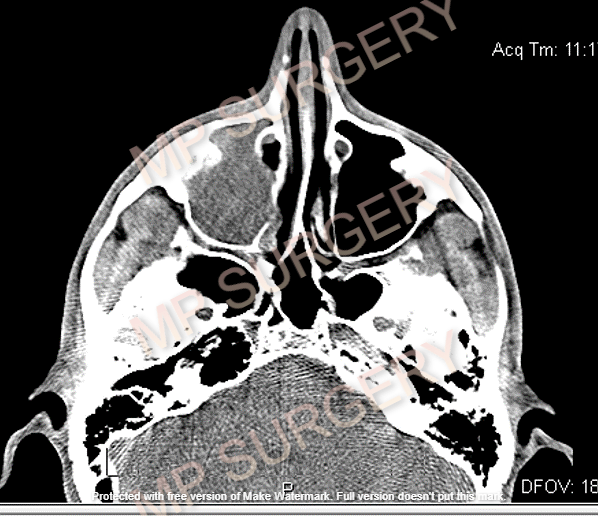

Οι ρίζες των οπισθίων δοντιών της άνω γνάθου βρίσκονται πολύ κοντά στο ιγμόρειο ή και μέσα στο ιγμόρειο.

Φλεγμονές ή κύστεις από τις ρίζες των δοντιών αυτών μπορούν να επεκταθούν μέσα στο ιγμόρειο και να προκαλέσουν οδοντογενή ιγμορίτιδα.

Πονοκέφαλος, πόνος στην άνω γνάθο, ρινική καταρροή, ρινική συμφόρηση (μπούκωμα), δυσκολία ρινικής αναπνοής, αίσθημα πικρού στην κατάποση μπορεί να υποδεικνύουν οδοντογενή ιγμορίτιδα.

Η αντιμετώπιση είναι χειρουργικός καθαρισμός ιγμορείου και αντιβιοτική αγωγή.